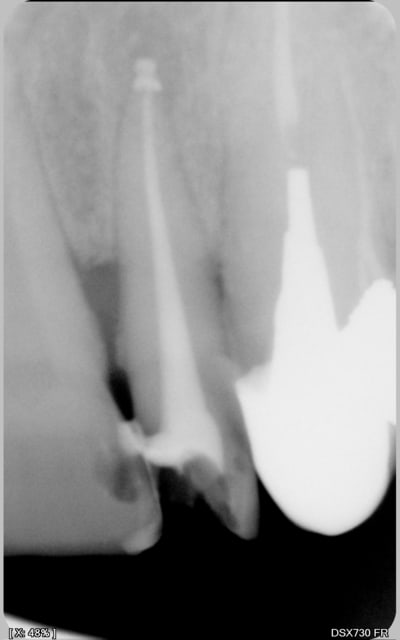

encore des radios,peut-etre assez moyen comme traitement...mais je vu pire...

les dernieres radios. patient en urgence ,abces... il voulait pas extraire la dent. j'ai lui bien explque et il a choisi de essayer de garder la dent. retrait,pas d'isolation avec la digue donc pas de tenon fibree,amalgam et screw post.traitement fait il ya 2 ans je crois.patient fidel de cabinet maintenent.

j'ai jamais utilise en roumanie l'amalgam et ca s'utilise pas du tout dans le cabinet du roumanie.